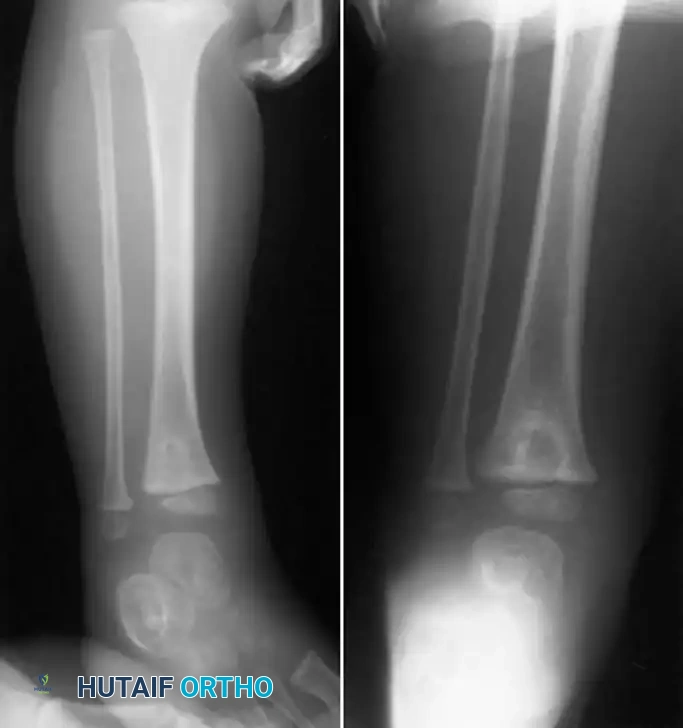

Fig. 16-9 Brodie abscess in right distal tibial epiphysis of 3-year-old child. The dense sclerotic rim is a classic hallmark of the host's attempt to wall off the low-virulence infection.

Organisms of low virulence are believed to cause the lesion. S. aureus is cultured in approximately 50% of patients, while in 20% of cases, the cultures remain completely sterile despite meticulous sampling. Because of the diagnostic uncertainty and the dense sclerotic bone that prevents antibiotic penetration, this condition frequently requires an open biopsy combined with thorough surgical curettage to establish the diagnosis and eradicate the infection.